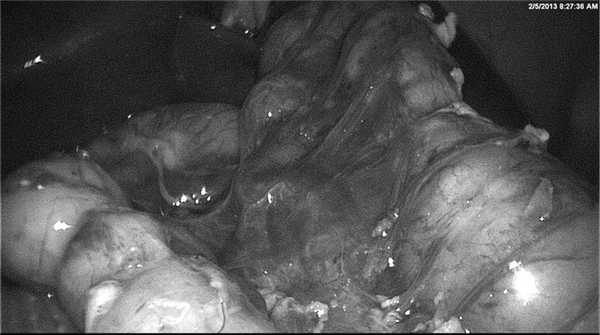

Если заворот «средней» кишки не сопровождался некрозом, то последующие этапы хирургического вмешательства повторяли шаги, которые используются при открытом варианте этой процедуры. Устраняли заворот, разделяли перидуоденальные спайки, перемещали слепую кишку в левую половину брюшной полости и фиксировали ее к сигмовидной кишке (см. рисунок). Использовали технику no touch (от англ. - без соприкосновения), т. е. без захвата стенки кишки, который может привести к ее травме. Конверсию к лапаротомии выполнили в 2 (12%) наблюдениях из-за недостаточной визуализации ключевых структур брыжейки на фоне заворота и нарушений мезентериального кровотока.

Интраоперационная фотография. Вид органов брюшной полости после выполнения операции Ледда. Слева находится выпрямленная двенадцатиперстная кишка, справа - толстая кишка, перемещенная в левую половину брюшной полости.